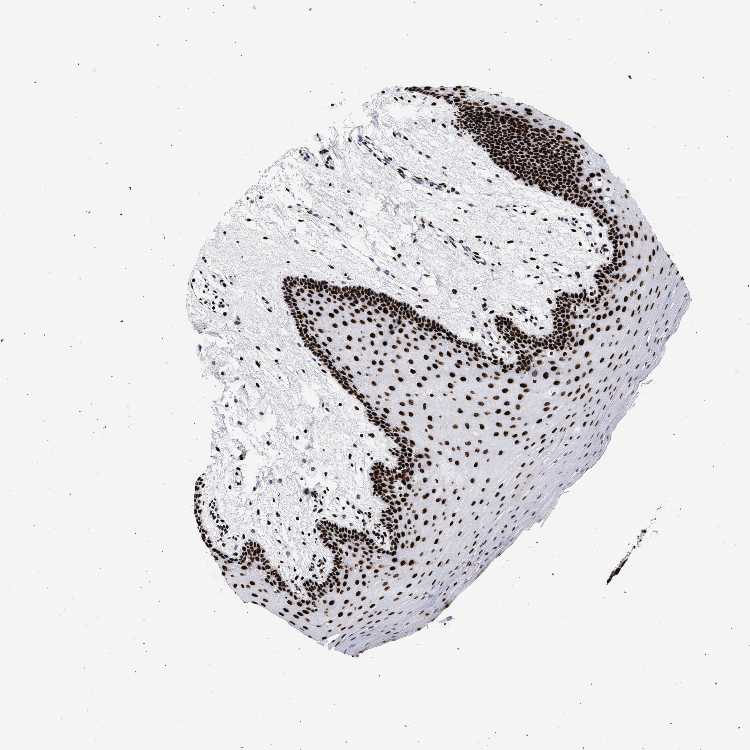

TISSUE PRIMARY DATA ORAL MUCOSA Show tissue menu

Oral mucosa

ORAL MUCOSA - Antibody stainingi

Antibody staining in the annotated cell types in the current human tissue is reported as not detected, low, medium, or high, based on conventional immunohistochemistry profiling in selected tissues. This score is based on the combination of the staining intensity and fraction of stained cells.

Each image is clickable and will lead to virtual microscopy that enables deeper exploration of all samples and also displays staining intensity scores, fraction scores and subcellular localization as well as patient and tissue information for each sample.

Antibody HPA001609Antibody HPA001666Antibody CAB010894

Squamous epithelial cells HighHighHigh